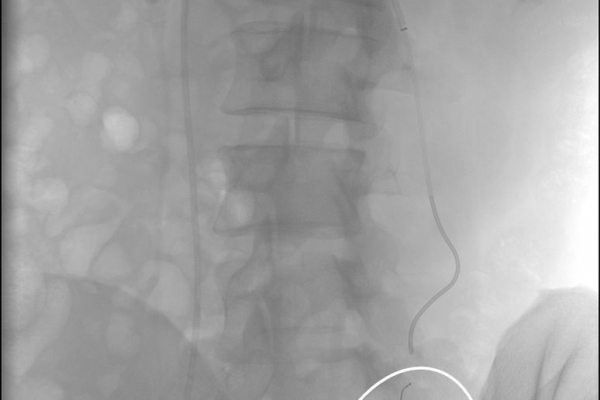

Συνοπτικά υπό την καθοδήγηση του αγγειογράφου, αναγνωρίζεταιτο παθολογικό αγγείο-αγγεία και με ειδικούς καθετήρες και μικροκαθετήρες, διοχετεύονται εμβολικά υλικάόπως μικροσφαιρίδια ή coils, ώστε να αποφραχθεί ή να μειωθεί η παθολογική αγγείωση.